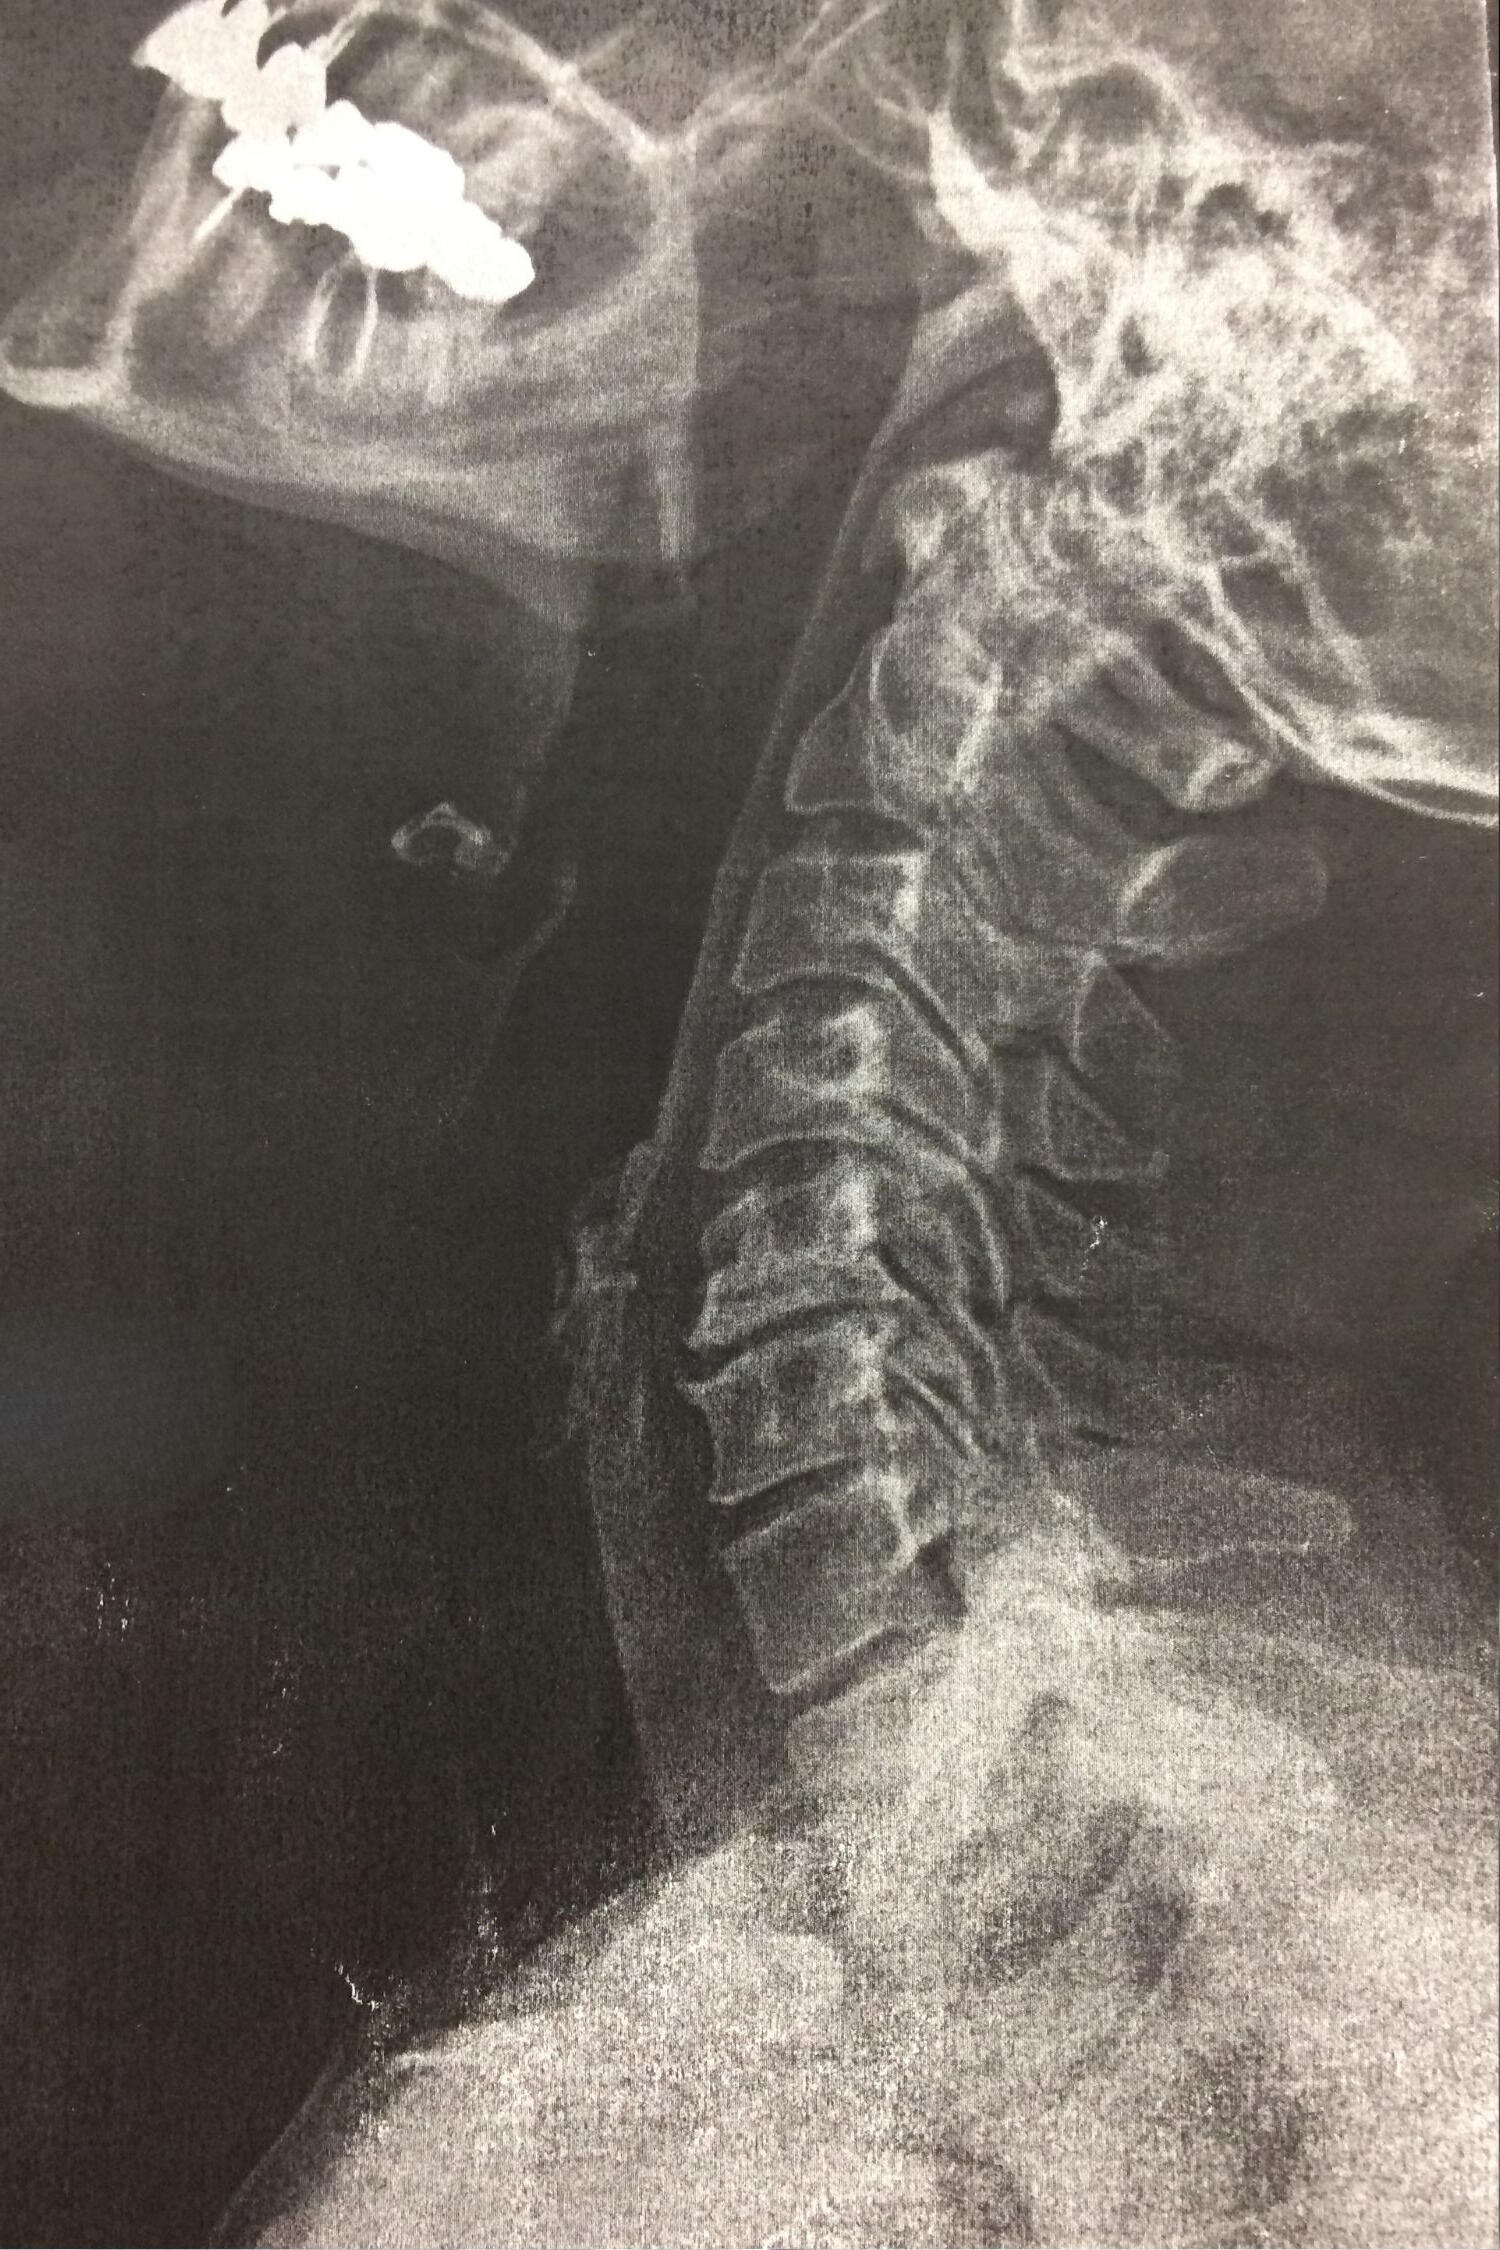

Improving posture, relieving pain, and restoring long-term function through corrective chiropractic care with science-based CBP® chiropractic that addresses the root cause—not just the symptoms.

Chiropractic BioPhysics® (CBP) uses proven, science-based methods to correct posture and restore proper spinal alignment—leading to long-term relief, better mobility, and improved overall health.Dr. John Thibodeau combines holistic care with personalized treatment plans designed to help your body heal and function the way it was meant to.

Corrects posture + spinal alignment

Uses traction, exercises, mirror-image adjustments

Creates long-term structural change

Reduces pain by fixing the root cause

Back and Neck Pain

Disc Issues

Posture Issues (Tech Neck, Rounded Shoulders)

Spondylosis

Scoliosis